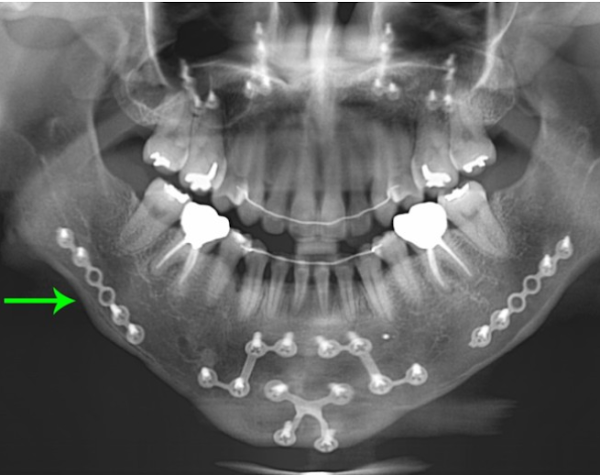

악(顎)교정술(턱의 위치나 모양을 변형시키는 수술)의 일종으로 윗턱인 상악(上顎)과 아랫턱인 하악(下顎)을 함께 수술하는 경우 양악(兩顎)수술이라 칭한다. 쉽게 말해 코 밑부터 아래턱 뼈 부분을 잘라내서 턱을 축소시켜, 얼굴을 바꾸는 치과 영역의 대수술.

양악수술을 하는 방법은 상악과 하악의 뼈를 잘라서 2개로 분리한 다음 정상 교합에 맞게 상악과 하악의 뼈를 이동시키고 이동된 뼈를 고정하는 방법이다. 뼈를 이동하는 대수술인 만큼 수술은 전신마취로 진행되며 보통 3일~7일 정도 입원하게 된다.

양악수술 한 사람의 엑스레이 상태